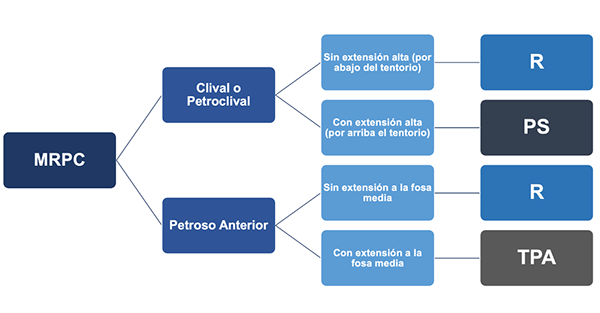

Actualmente, no existe un consenso en la elección de un abordaje quirúrgico ideal para acceder a la región petroclival; sin embargo, la extensión del tumor, la relación con el tentorio y el compromiso neurológico pueden inclinar la balanza hacia algún tipo de abordaje. Muchos cirujanos han propuesto herramientas para la elección de un abordaje específico, pero éstas pueden perder valor cuando se individualiza cada caso en particular. Recientemente Guinto et al. propusieron un sistema de medición que evalúa las bondades del abordaje retrosigmoideo en el manejo de los meningiomas petroclivales puros dependiente del grado de desplazamiento y posición del pedúnculo cerebeloso medio en relación al tumor. Los autores del presente trabajo consideran que el abordaje debe estar basado principalmente en la zona de implantación de tumor, que puede ser clival, petroclival o petrosa anterior, en la relación que existe entre la lesión y el tentorio, y en la extensión o no a la fosa media (Figura 12). Para las zonas clival y petroclival, el abordaje retrosigmoideo es preferido cuando el tumor se ubica por debajo del nivel del tentorio. En caso de una extensión tumoral alta, por arriba del tentorio, el abordaje presigmoideo es de mayor utilidad. Para los tumores con implantación en la zona petrosa anterior sin extensión a la fosa media una buena opción es el abordaje retrosigmoideo, en general utilizando el fresado del tubérculo suprameatal. Si existe extensión a la fosa media el abordaje indicado es el transpetroso anterior En algunas situaciones muy puntuales es necesario combinar abordajes para resolver de mejor manera el caso (Figura 13).

Figura 13. Algoritmo de elección de una ruta de abordaje quirúrgica en MRPC. Para la elección de un abordaje quirúrgico los MRPC pueden agruparse en petrosos anterior o clivales y petroclivales por su cercanía anatomíca. En el caso de los meningiomas petrosos anterior se debe evaluar si tienen o no extensión a la fosa media para decidir entre un abordaje retrosigmoideo (R) o un abordaje transpetroso anterior (TPA). Para los meningiomas clivales y petroclivales se debe tener en cuenta su relación con el tentorio, en caso de sobrepasarlo un abordaje presigmoideo (PS) sería la elección.